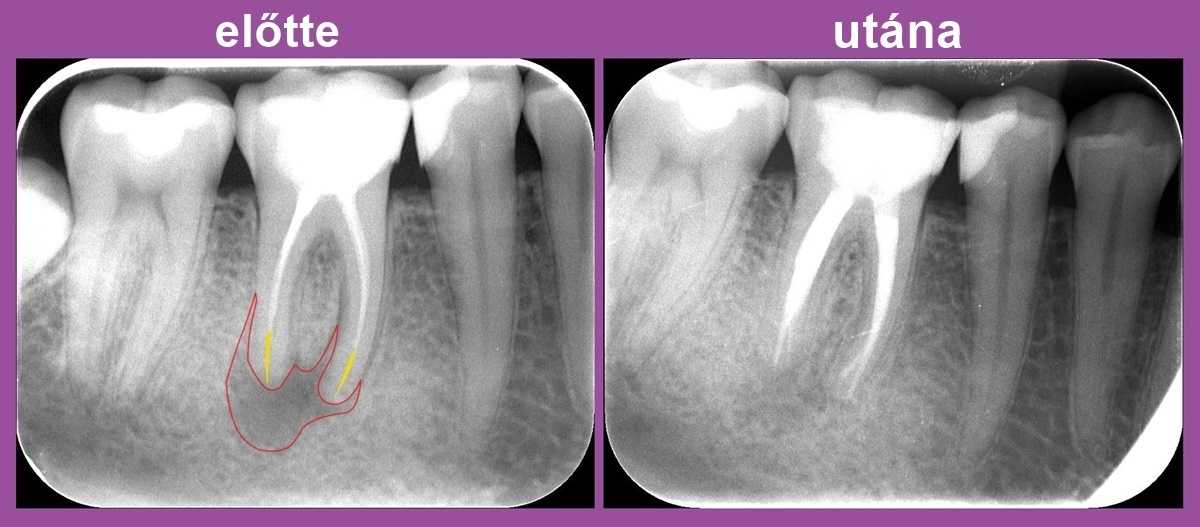

A csatornák a fog gyökereiben futnak: vannak egygyökerű, egycsatornás fogak (mint általában a frontfogak vagy a szemfog), vannak egygyökerű, ám többcsatornás fogak (például az első és a második kisőrlők), és a többgyökerű, többcsatornás fogak (a nagyőrlők, köztük a bölcsességfogak is ide tartoznak).

A mikroszkópos kezelés olyan eredményes lehet, hogy amikor a hagyományos kezelés nem segített, még olyankor is sikeresen meggyógyíthatja a beteg fogat.